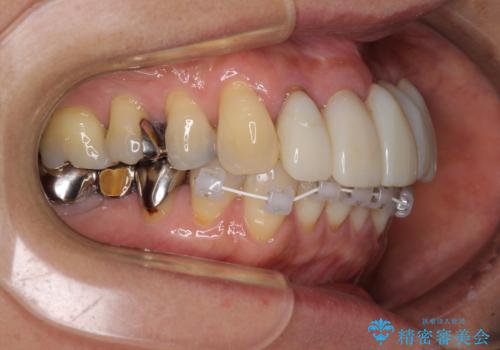

前歯のみならず、奥歯の銀歯や下顎前歯のデコボコなど、色々と気になる部分を治したいとのことでした。

下顎と上顎臼歯部については矯正治療を行い、奥歯の欠損部位はオールセラミックブリッジを、その他の銀歯はセラミックインレーなどにより治療を行うこととしました。